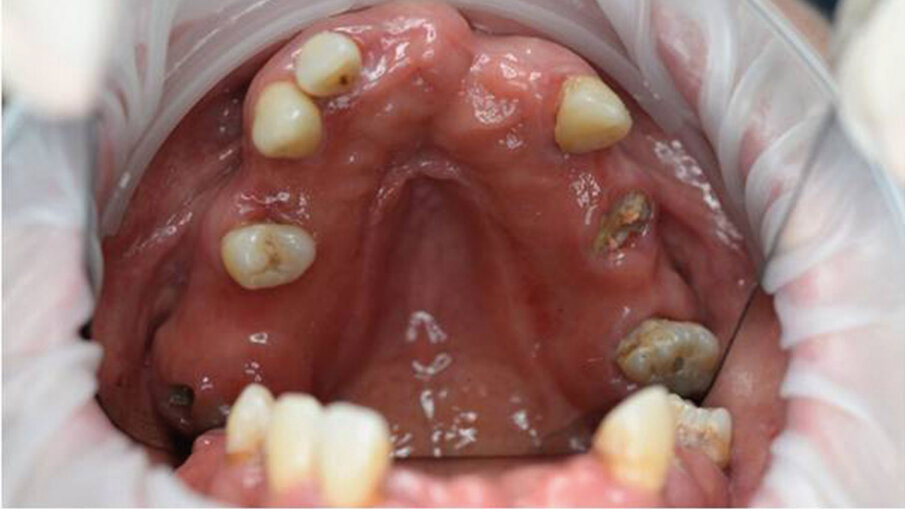

La paziente, una donna di 69 anni in buono stato di salute generale e senza terapie farmacologiche in corso, presentava una condizione orale fortemente compromessa caratterizzata da molte estrazioni dentali pregresse, una dentatura residua gravemente danneggiata da carie distruttive e numerosi processi infiammatori apicali e periapicali, che comportavano una severa mobilità della maggior parte dei denti presenti (Figg. 1, 2). La paziente utilizzava già una protesi parziale mobile superiore, la quale aveva causato nel corso degli anni un’ampia area di decubito palatale (Fig. 3). Data la compromissione estetica e funzionale dell’intero apparato masticatorio, si è deciso di procedere con una riabilitazione mediante una protesi avvitata supportata da impianti.